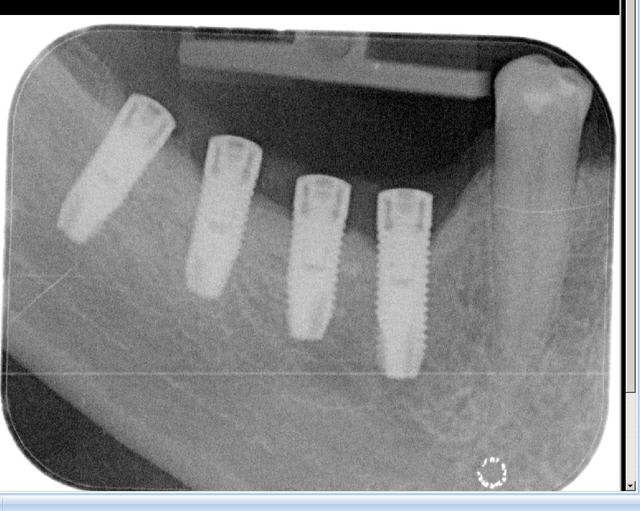

une retro alveolaire ?

"pas de bras, pas de chocolat"...pas de rétro, pas d'identification

une pano déforme beaucoup et ne nous donne pas assez de détails sur "l'anatomie" des implants, bref çà ne sert à rien dans ce cas de figure qu'est l'identification d'implants...

tout à fait d'accord avec pluton, une retro est indispensable pour répondre.

Je n'ai pas pu avoir mieux.

Je pense à de l'astra

non, c'est pas une connexion type Astra

dommage que ta radio ne soit pas plus nette, çà m'aurais permis d'être plus performant...

moi je pencherais plus sur un Alphabio ou même encore plus probable un AB dental

http://osseosource.com/dental-implants/product_info.php?products_id=39